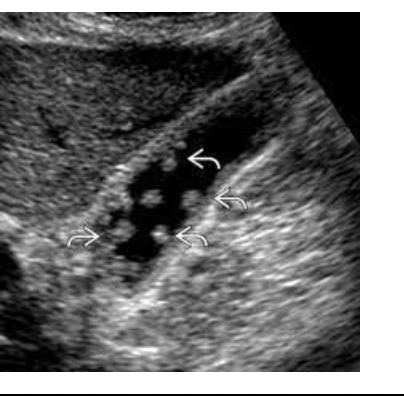

What pathology is in the image below ?

Cholesterlosis/Polyps - Well defined, tissue projection, multiples, do not shadow, fixed, immobile